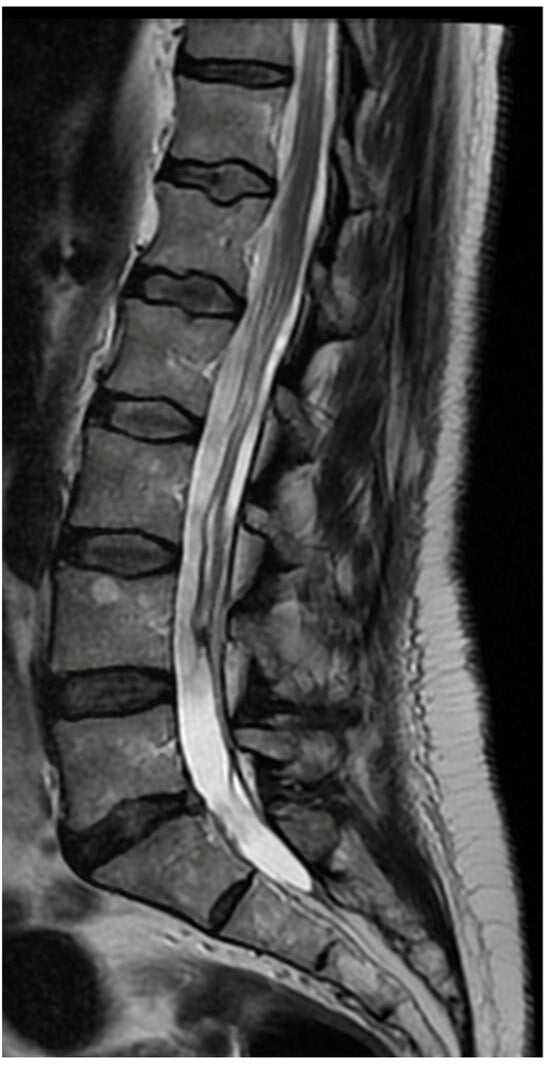

3.4. Case 1: Transient Cauda Equina Syndrome Due to Subdural Hematoma